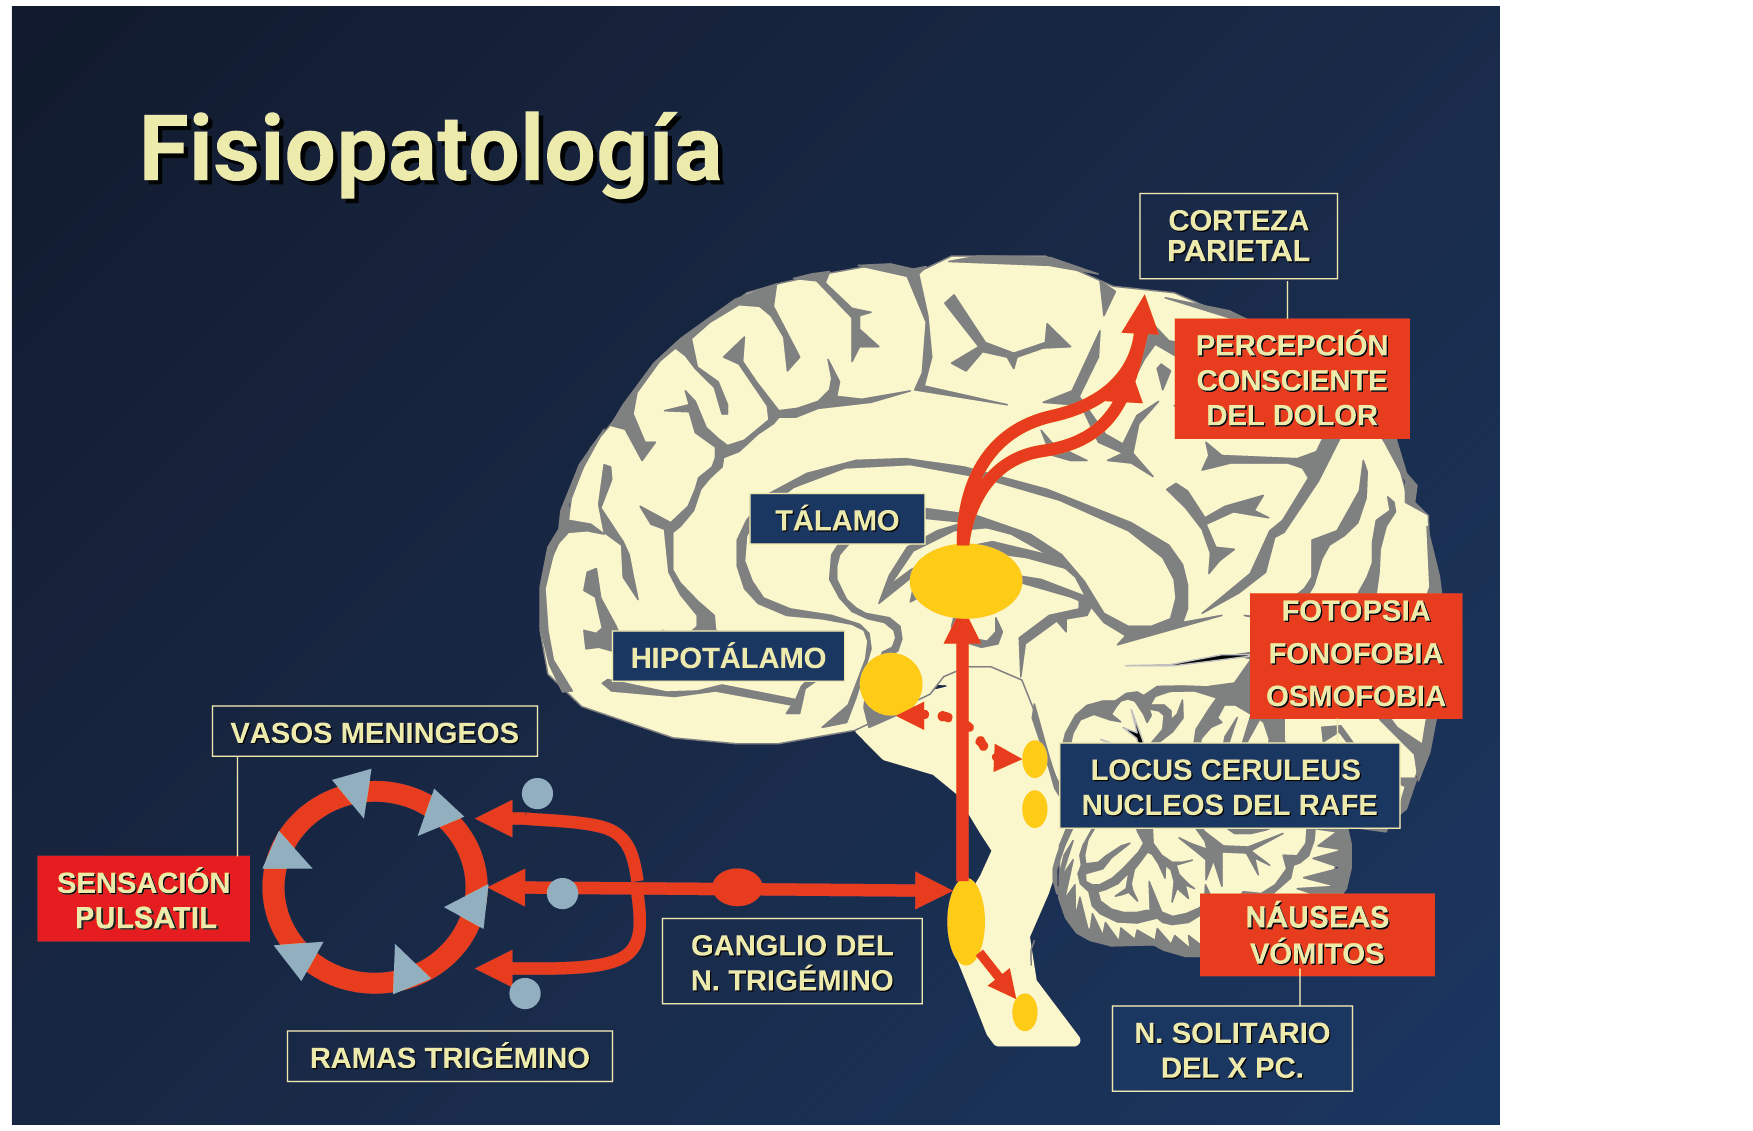

Todo lo mencionado contribuye al fenotipo del migrañoso y son vías que continuamente se están explorando para el desarrollo de nuevas terapias agudas y preventivas del dolor, más seguras y eficaces. Sin embargo, existe una controversia que gira en torno a dos cuestiones: la iniciación y el origen del dolor además de que todavía no se conoce el origen de los mecanismos neuronales que subyacen a la condición primaria en las personas susceptibles. Definitivamente la migraña implica la activación y sensibilización de las vías trigeminovasculares, así como el tronco cerebral y los núcleos diencefálicos(88). La vía aferente comienza en las aferentes vasculares nociceptivas de la duramadre que están para advertir, no para localizar. Su proyección al tálamo y la corteza y como se regula esta vía en cada nivel y por múltiples sistemas, ofrece la posibilidad de comprender los síntomas complejos y orientar las terapias. Los ataques comienzan como síntomas premonitorios, dificultad para concentrarse, bostezos, fluctuaciones del humor; y cambios homeostáticos, como la alimentación y el equilibrio de líquidos, que pueden incluir sensibilidades más generalizadas, como fotofobia y fonofobia. La fase premonitoria da paso a la fase de dolor con el sufrimiento acompañante y termina en una fase posdrómica de sentirse agotado por la experiencia. (Figura 1)

La fisiopatología de la migraña había surgido de una consideración histórica de los “humores” hasta mediados del siglo XX con la ahora desaparecida Teoría Vascular. Pero aún se podría decir que hay tres preguntas: ¿por qué, cómo y cuándo? Por qué: se acepta en gran medida que la migraña es una tendencia heredada del cerebro a perder el control de sus vías de acceso de impulsos. Cómo: la ahora clásica vía aferente nociceptiva vascular de la duramadre del trigémino ofrece una hoja de ruta del ataque. Cuándo: los ataques de migraña surgen debido a un trastorno del procesamiento sensorial del cerebro que probablemente sea cíclico, influenciado por la genética y el medio ambiente.

En la primera fase (figura 3), premonitoria, que precede a la cefalea, los sistemas del tronco encefálico y diencefálico modulan las señales aferentes, la fotofobia a la luz o la fonofobia al sonido, comienzan a disfuncionalizarse y eventualmente a evolucionar a la fase de dolor y con el tiempo a la fase de resolución o posdrómica. Aproximadamente en un tercio de los pacientes con migraña, sus ataques están asociados con déficits neurológicos, que incluyen perturbaciones corticales, denominadas colectivamente aura de migraña(3).

Un principio importante de esta teoría es que el desencadenante principal de la migraña proviene de la periferia, en los vasos sanguíneos de la duramadre, con la activación del sistema trigeminovascular proveniente del disparo de las neuronas trigeminales periféricas de primer orden en respuesta a una lesión nociceptiva o señales provenientes de las meninges que liberan mediadores neuroinflamatorios. La activación sostenida de las neuronas nociceptivas meníngeas durales provoca la activación secuencial y la sensibilización de las neuronas trigeminovasculares de primer orden (nociceptores periféricos), segundo orden (a nivel del TCC-complejo trigémino cervical) y tercer orden (trigeminotalámico), (Figura 5) así como la activación ascendente del cerebro, tallo y otras estructuras diencefálicas(97).

Se cree que esta activación secuencial explica la naturaleza pulsátil del dolor en la migraña, la hipersensibilidad sensorial nociceptiva, los síntomas neurológicos asociados que incluyen náuseas, vómitos, alteración de la alimentación y el sueño, así como la alteración cognitiva. Clínicamente, sin embargo, hay muchas lagunas. Los síntomas premonitorios en la migraña pueden estar presentes 24 a 48 h antes del dolor de cabeza y están representados por cambios en la activación en las regiones del cerebro medio e hipotalámico. Los desencadenantes de la migraña, como la privación de sueño y alimentos y el estrés, están bajo control homeostático.

El dolor de la migraña es, sin duda, una consecuencia de la activación o la percepción de la activación de los mecanismos neurovasculares, de allí que sea considerado un trastorno puramente neuronal. Mucha evidencia indica que los cerebros de las personas con migraña pueden ser diferentes en la forma en la cual responden a la estimulación sensorial, incluso interictalmente(102). Una hipótesis alternativa y que lo abarca todo es que el cerebro está en el centro del desencadenamiento de la migraña. Más que una activación secuencial de diferentes regiones del cerebro, la migraña es un trastorno del cerebro y por lo tanto, se considera un “estado cerebral”, que es una consecuencia de cambios o disfunciones en las regiones del tronco encefálico y el hipotálamo, que contribuyen a su vez a cambios a nivel celular y vascular en muchas regiones del cerebro. Esta hipótesis establece que la migraña puede describirse mejor como una consecuencia de la disfunción en el tronco encefálico y los núcleos hipotalámicos que normalmente modulan o activan las entradas sensoriales, como el tacto, la luz, los sonidos y los olores. Estos núcleos del tronco encefálico y del hipotálamo pueden considerarse “mediadores de la migraña” y su disfunción puede llevar al fracaso de los mecanismos de integración y filtrado cerebrales, lo que da como resultado la percepción de activación de los sistemas sensoriales en condiciones normales. La compleja red de conexiones entre las regiones del tronco encefálico, que incluyen PAG, RVM, locus ceruleus y SuS y los núcleos diencefálicos, incluidos el hipotálamo, el tálamo y la corteza, pueden conducir a la generación de síntomas a través de la misma disfunción central. La disfunción en estas regiones, a través del control descendente del tráfico nociceptivo trigeminovascular, puede conducir a la percepción del dolor de cabeza a través de la palpitación de los vasos normales y la disfunción continua puede conducir a la sensibilización central de las neuronas trigeminovasculares y la exacerbación del dolor con la actividad física normal, así como en la piel: alodinia cefálica y extracefálica. La convergencia de entradas sensoriales en el tálamo que se proyectan a la corteza puede explicar la hipersensibilidad a la luz, los sonidos y los olores. La misma disfunción puede conducir a cambios homeostáticos, controlados por el hipotálamo, relacionados con el sueño, la alimentación y la actividad. La alteración general de la función cortical y subcortical puede desencadenar eventos como el aura migrañosa y extenderse a una incapacidad general para funcionar correctamente. Los factores genéticos heredados juegan claramente un papel en la predisposición a la susceptibilidad a la migraña, al igual que el papel de los desencadenantes potenciales de la migraña, cuyo vínculo común parece jugar en el corazón de la homeostasis cerebral en el hipotálamo y el tronco encefálico. (figura 7).

La relevancia del tronco encefálico para la fisiopatología de la migraña está respaldada por estudios clínicos e investigaciones básicas. En presencia de la crisis dolorosa, se ha demostrado que hubo un aumento del flujo sanguíneo cerebral en el mesencéfalo, la protuberancia rostral dorsal cerca del PAG y los núcleos del rafe(22) y además se localizaron varios síntomas de migraña en diferentes áreas del cerebro concomitantemente con la experiencia de dolor de cabeza en la corteza cingulada, fotofobia en la corteza de asociación visual y fonofobia en el auditivo, corteza de asociación. Estas señales desaparecieron después de la terminación exitosa del ataque. Sin embargo, el aumento de flujo sanguíneo cerebral en el tronco encefálico persistió en la fase temprana sin dolor. Por lo tanto, esta estructura refleja no solo un síntoma de migraña, sino que también indica una disfunción de importancia para la generación o el mantenimiento del ataque de migraña en sí.

En el cerebro de las personas con migraña se activan distintas áreas, las cuales desempeñan roles diferentes dentro del complejo sintomático ya sea desencadenando el ataque, generando el dolor o participando en algunos de los síntomas neurológicos asociados que ocurren durante un ataque. Desde el punto de vista fisiológico y fisiopatológico se ha aprendido sobre la asociación de estas diferentes regiones cerebrales entre sí, definiendo la participación de núcleos diencefálicos, del tronco encefálico y áreas corticales. También se ha podido determinar cómo se procesa la información nociceptiva de las estructuras craneovasculares, lo que da como resultado la percepción del dolor de cabeza durante la migraña, así como los síntomas sensoriales neurológicos asociados.

El dolor de cabeza asociado con un ataque de migraña, puede incluir la región frontal, temporal, parietal, occipital y cervical alta, es consecuencia de la activación del sistema trigeminovascular. (Figura 10)

Por lo tanto, se cree que la naturaleza intensa y pulsátil del dolor en la migraña es el resultado de la activación, o la percepción de activación, de estas entradas nociceptivas de las estructuras intracraneales y extracraneales, que convergen y se transmiten a través del TCC. (Figura 17)

Toda la información nociceptiva de las estructuras craneovasculares se transmite a través del TCC y mediante conexiones ascendentes a otras áreas del tronco encefálico y el diencéfalo, involucradas en el procesamiento del dolor y otra información sensorial. La activación de la vía antes mencionada contribuye a la percepción del dolor durante la migraña y también a los síntomas autonómicos, endocrinos, cognitivos y afectivos que duran todo el episodio migrañoso.

El procesamiento del dolor es complejo y está mediado por una red de estructuras neuronales que incluyen la corteza cingulada, las ínsulas y el tálamo(28). El tálamo está en el corazón del procesamiento central y la integración de la información nociceptiva y se considera un centro de retransmisión para manejar la información sensorial entrante e incluso modularla. Se cree que la llamada “matriz del dolor”, que incluye el tálamo, así como las áreas somatosensoriales primarias (S1) y secundarias (S2), la corteza cingulada anterior (CCA) y la corteza prefrontal, está involucrada en la integración de todos los sentidos, respuestas afectivas y cognitivas al dolor y se activan durante el procesamiento nociceptivo(28). (Figura 18)

Siendo el tálamo el centro principal para el procesamiento de la información nociceptiva sensorial en el cerebro, la transmisión de esta información para su procesamiento en las estructuras corticales donde los individuos la perciben es un factor clave. (Figura 18) Los tratamientos agudos como los “triptanos” (agonistas de los receptores 5-HT1B/1D)(29) y los antagonistas de los receptores CGRP(30) pueden inhibir las entradas nociceptivas durales agudas. Del mismo modo, los preventivos de la migraña propranolol(31), valproato de sodio(32) y topiramato(33)también pueden inhibir las entradas trigeminotalámicas nociceptivas durales en el VPM (Núcleo ventral posteromedial).